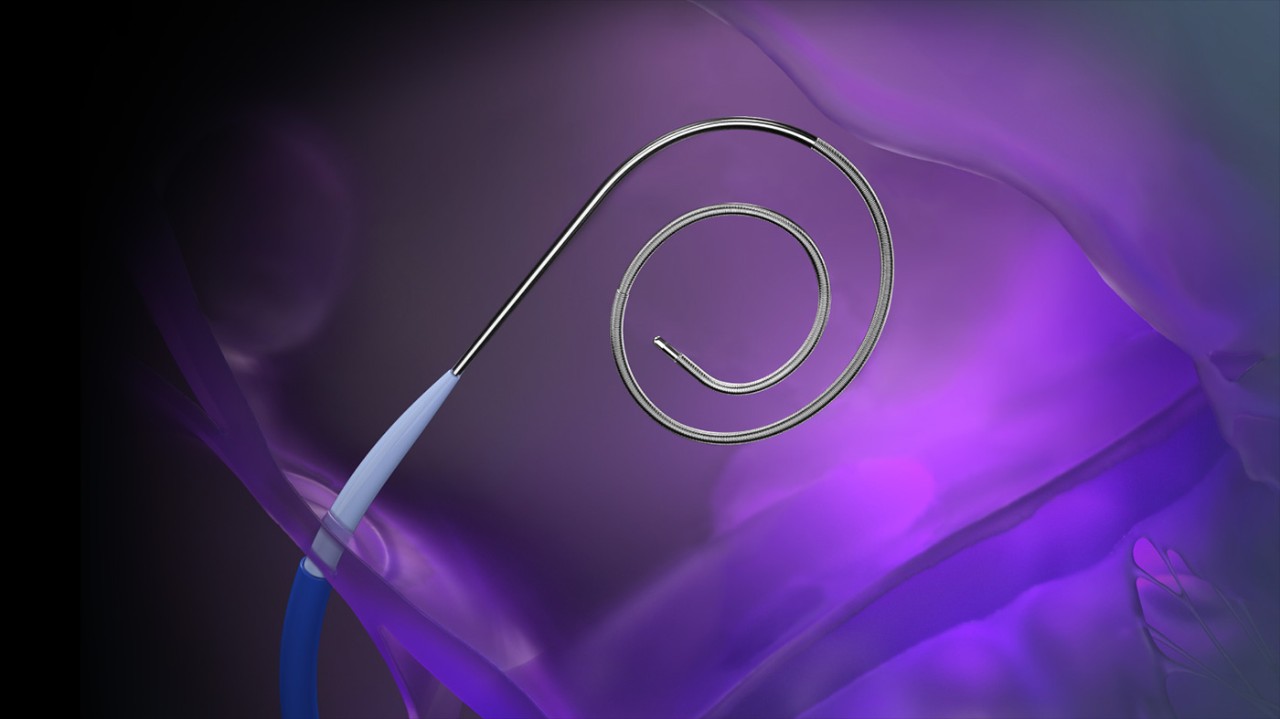

VersaCross Access Solution with pigtail VersaCross RF Wire.

• VersaCross RF Wire (j-tip or pigtail)

Tip configurationsJ-tip, pigtail

Curve shape9 mm (j-tip), 24 mm (pigtail)

Wire diameter0.035 in (0.89 mm)

Overall length180 cm, 230 cm

VersaCross RF Wire in j-tip and pigtail configurations.

VersaCross RF Wire

RF wire length: 180 cm, 230 cm

Wire diameter: 0.035 in (0.89 mm)

Curve diameter: 9 mm (j-tip), 24 mm (pigtail)